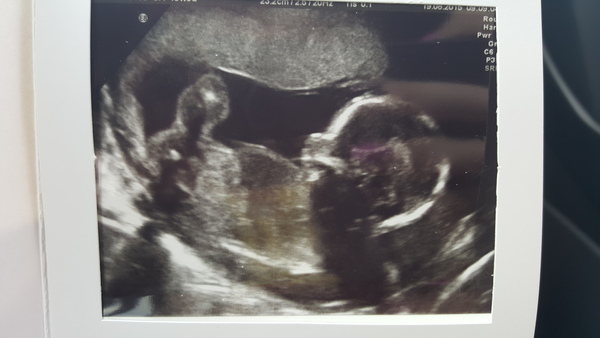

Thanks for the kind words too, I'm feeling a bit more positive today and just heard the baby's hb at my mw appt